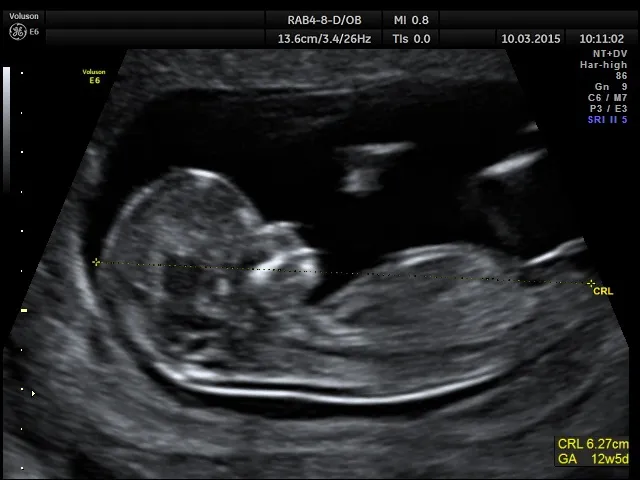

Badanie USG w I trymestrze: najdokładniejszy sposób na weryfikację wieku ciąży

Obecnie najdokładniejszą metodą określenia wieku ciąży jest badanie USG wykonane w pierwszym trymestrze, najlepiej między 7. a 12. tygodniem. Kluczowym pomiarem jest wtedy długość ciemieniowo-siedzeniowa (CRL crown-rump length), czyli długość płodu od czubka głowy do pośladków. Na tym etapie rozwoju wszystkie płody rosną w bardzo podobnym tempie, co pozwala na niezwykle precyzyjne datowanie. Jeśli istnieje rozbieżność między terminem wyliczonym z ostatniej miesiączki a tym z USG, to właśnie wynik badania ultrasonograficznego jest uznawany za bardziej wiarygodny i staje się podstawą do dalszego monitorowania ciąży.